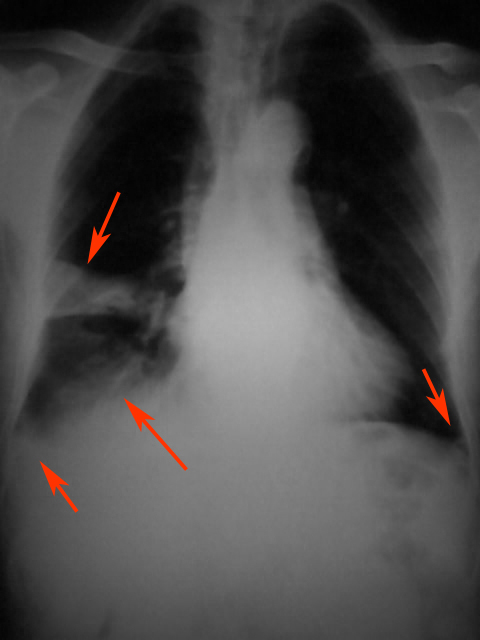

患者男,54岁,咳嗽咯痰伴右胸疼痛5天余.体温正常,一般情况尚可,否认咯血史

胸膜增厚,右膈模糊,感染

右中叶片状均匀高密度影,边界清楚,肺门区为见明显肿大的阴影,考虑右中叶综合征,更倾向于炎症,完善必要的实验室检查。

右中叶片状均匀高密度影,边界清楚,考虑右中叶综合征,做个ct吧

右肺中叶占位性病变伴右肺中叶不张。

右肺中叶外段炎症,右胸腔积液

右肺中叶炎症,性质待查.右胸腔积液

右肺中叶炎症,右侧胸膜炎

考虑右肺中叶炎症,右侧胸膜炎,建议抗炎后复查

右中叶综合征,建议抗炎后复查

右肺中下叶炎症并胸膜炎

综合观察.叶间积液并包裹性积液.右下炎症,胸膜肥厚.

右侧胸腔积液伴右侧水平裂叶间积液;胸膜肥厚;左肋膈角改变,考虑胸膜粘连可能大.各位老师好!能结识此网站是我的荣幸!

右肺中叶炎症并膨胀不全,右侧胸膜炎。